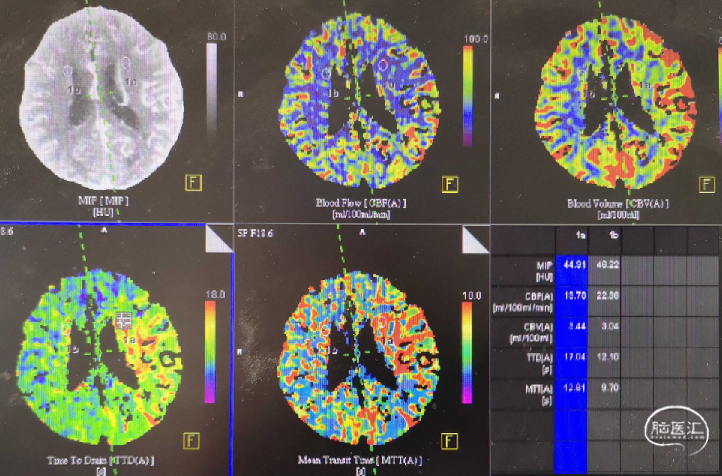

病史:患者自3天前无明显诱因出现言语不清,右侧肢体无力,跌倒在地,持续约数分钟后恢复正常,可自行行走,共发作两次,症状类似,后右侧肢体无力症状持续存在,遂至**医院要就诊,行头颅CT检查未见明显异常,予以阿加曲班等药物应用,效果欠佳。5小时前上述症状较前明显加重,出现意识不清、右侧肢体偏瘫,无法站立、不能持物,完善头颅MRA示左侧颈内动脉、大脑中动脉闭塞。22:10至我院就诊,查CT示左侧大脑中动脉高密度影,左侧内囊低密度影。CTP示左侧大脑半球低灌注代偿期。

术前CTP:CBF减低,CBV 稍增高,TTP、MTT延长,核心梗死区小。患者临床症状进行性加重、外院MRA显示大血管急性病变,机械取栓治疗指征明确。